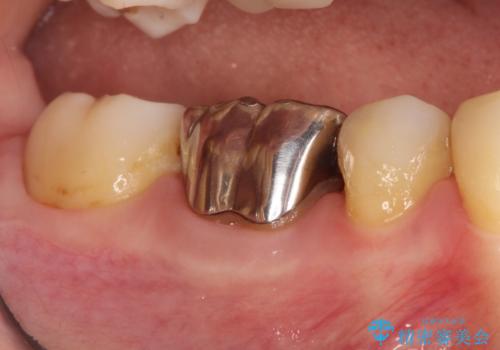

- 定期検診にて虫歯を認めた患者さんです。

患者さんの希望により、修復物の割れる心配が少ないゴールドインレーでの治療を行いました。

ゴールドインレーの場合、歯質とのすり合いを行い適合性を高めています。